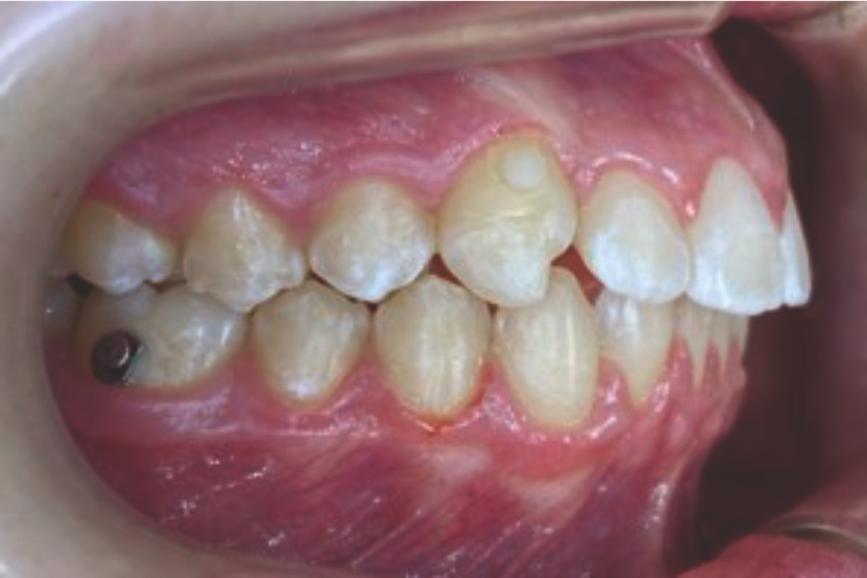

Chief complaint: We present the case of a 12-year-old female patient who came for an orthodontic evaluation, motivated by a family history of treatment. Clinical and radiographic analysis revealed a skeletal Class II malocclusion with molar and canine relationships also in Class II, moderate crowding in both arches, a deviation of the dental midline, and ectopic eruption of tooth 13. No functional issues with breathing or swallowing were observed, and oral health was generally good. A slight mandibular retrusion was noted in the soft tissue profile. A treatment plan was proposed using the Angel Aligner Pro system, aiming to correct dental misalignments and improve facial harmony through a minimally invasive, growth-adapted approach.

Clinical examination and diagnosis

- Woman ; 12/3 years

- Skeletal Class II

- Molar and canine Class II

- Upper and lower dentoalveolar compression

- Increased overjet and overbite

- Upper midline deviated 0,5 mm to the right

- Moderate upper and lower crowding